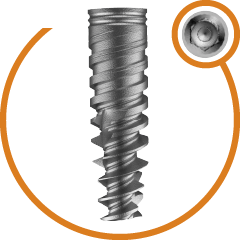

Completely Polished body of zygoma to avoid peripathogen and prevent

sinus related complication

Progressive single spiral threads. Anti- rotational cuts to improve primary stability. Higher Bone Implant contact.. More Resistance to Tensile & Compressive forces. Surface treated thread to achieve better secondary stability.

Allow insertion in minimum 1-2 drilling. Optimum Zygomatic bone engagement. Micro-polished tip without any sharp edges.